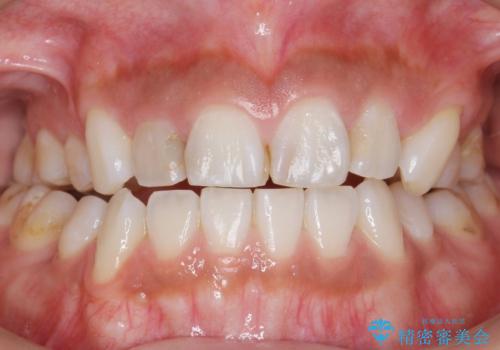

矯正せずに隙間を閉じることができ、ご満足頂けました。

セラミッククラウンの審美的な仕上がりと咬み心地に喜んで下さいました。

クラウンの種類:オールセラミッククラウン スタンダード